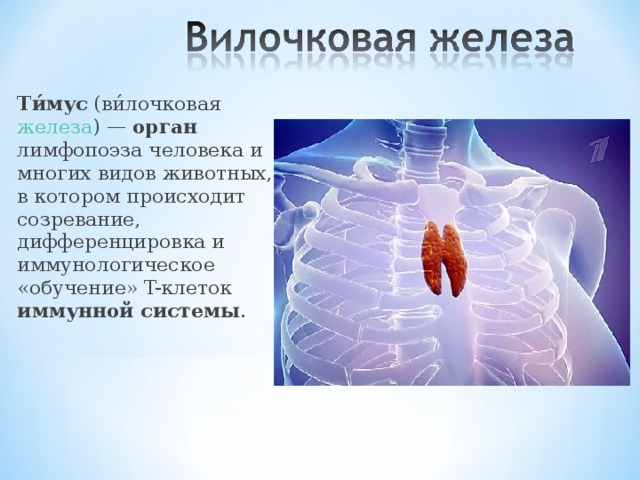

Фотографии вилочковой железы тимуса: структура и функции

Раздел: Снимки-откровения